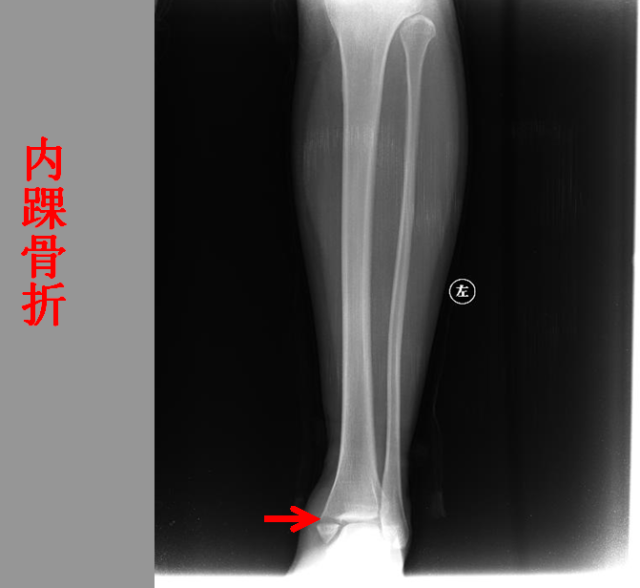

骨折篇

定义:骨折{Fracture}是指骨的完整性和连续性的折裂或粉碎。包括创伤性骨折、疲劳性骨折和病例理性骨折。 临床上以创伤性骨折*常见。